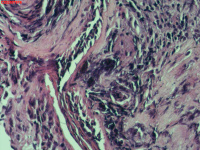

右肺上叶开口处 气管镜咬检

性别

男

年龄

65岁

临床诊断

一般病史

肺TB

标本名称

大体所见

右肺上叶开口上缘处可见肉芽增生,予咬检。

感觉:炎性纤维组织增生